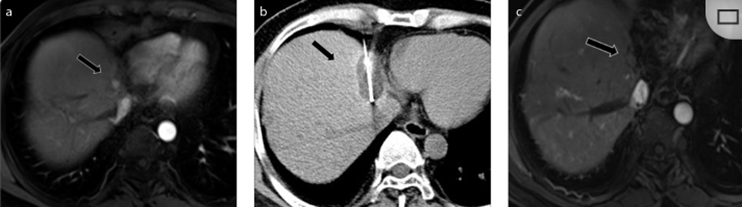

CT引导的冷冻消融

51岁男性患者,肝移植后复发病例

(a) 射频消融后在病变边缘显示残余增强。

(b) 冷冻消融术中影像显示冰球完全覆盖病变。

(c) 19个月后随访,没有发生局部肿瘤进展。